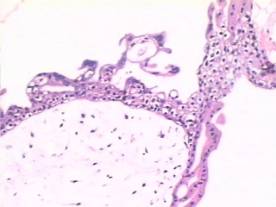

肉眼觀,癌結節呈單個或多個,位於子宮的不同部位,大者可突入宮腔,常侵入深肌層,甚而穿透宮壁達漿膜外。由於明顯出血壞死,癌結節質軟,色暗紅或紫蘭色。

鏡下,瘤組織由分化不良的細胞滋養層和合體細胞滋養層兩種瘤細胞組成,細胞異型性明顯,核分裂像易見。兩種細胞混合排列成巢狀或條索狀,偶見個別癌巢主要由一種細胞組成。腫瘤自身無間質血管,依靠侵襲宿主血管獲取營養,故癌組織和周圍正常組織有明顯出血壞死,有時癌細胞大多壞死,僅在邊緣部查見少數殘存的癌細胞。癌細胞不形成絨毛和水泡狀結構,這一點和侵蝕性葡萄胎明顯不同。

絨癌的病理特點是大片增生和分化不良的滋養細胞侵犯子宮肌層和血管,仔細檢查未發現有絨毛或葡萄胎樣結構,常伴有遠處轉移,最常見轉移部位是肺。